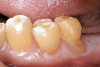

Characteristics of damage to tooth structures caused by acidity include wear on the occlusal surfaces of molars and a saucer shape on the cusps of molars (perimolysis).12 The erosion can vary from minor and subtle changes on the tooth surface, ie, loss of luster, a dull or matted look, to cupping on occlusal surfaces or incisal edges, which may extend to dentin. Usually, the erosive lesions demonstrate greater width than depth. When combined with abrasive forces or stresses, the tooth surface loss may occur at a faster rate (Figure 2, Figure 3, Figure 4 and Figure 5).

Figure  4  Possibly a combination of erosion and abrasion.

Figure 4